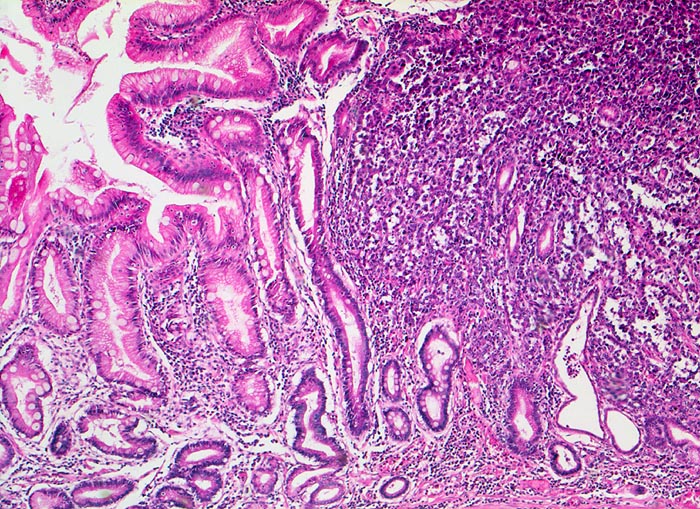

PathoPic – image database / PathoPic ID 5063 - Magenfrühkarzinom

Magenfrühkarzinom

Links im Bild die Magenschleimhaut mit intestinaler Metaplasie (zahlreiche Becherzellen). Diffuse Tumorinfiltration mit Verdrängung und Umwachsung der ortsständigen Magendrüsen rechts im Bild. Der abgebildete Karzinomanteil ist gering differenziert. Die hochgradig atypischen Tumorzellen bilden nur andeutungsweise erkennbare Drüsenschläuche.

Endoskopische Kontrolle bei Patient mit bekannter chronischer Gastritis.